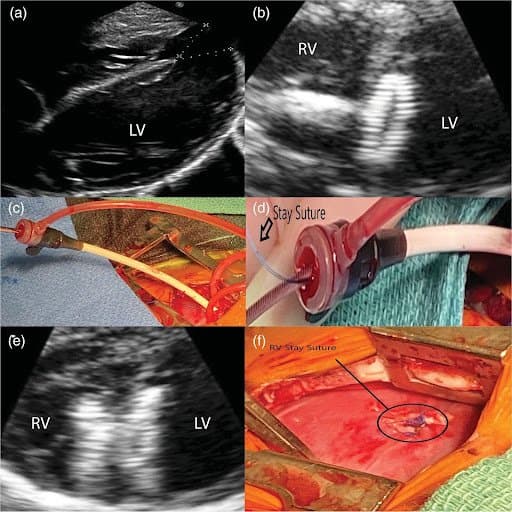

Pre-procedural trial run on a 3D model. (a) Suture through the right ventricular (RV) side of the muscular ventricular septal defect (VSD) device. (b) Suture threaded through the loader. (c) Delivery system attached to muscular VSD device. (d) Sheath advanced into anterior RV wall. (e) Sheath in RV demonstrating RV disc deployed. (f) Device released with stay sutures seen going from the RV disc and out via the anterior RV ready to be secured

(a) Apical ventricular septal defect (VSD) measurements via transesophageal echocardiogram(TEE) 14 mm×12 mm. (b) Left Ventricle (LV) disc of the device seen released with the delivery system still attached. (c) 9 Fr sheath in the anterior right ventricular (RV) with delivery system. (d) Suture and delivery system visualized going through sheath. (e) TEE of deployed muscular VSD device. (f) Anterior RV stay suture tied to a horizontal mattress autologous pericardial pledgets 5–0 Prolene on the apical surface of the RV.

“Computed tomography angiography (CTA) demonstrated a 12×14 mm apical muscular VSD. A 3D model was constructed using the end-diastolic images from the CTA, and the blood pool was segmented using ITK-SNAP2 at 1:1 scale. A 1 mm hollow shell was created around the blood pool and printed with part of the ventricular free walls removed on a Form 3 Stereolithography (SLA) Printer (Formlabs Somerville, MA) with Elastic Resin.”

“A 3D model was also manufactured to enhance the understanding and visualization of the patient's anatomy, and augment the decision making for both the interventionist and the surgeon. Furthermore, the 3D model allows for a risk-free environment to rehearse the procedure in order to troubleshoot anticipated difficulties preoperatively. Although it may have been reasonable to attempt a pure transvenous approach, the 3D model further enhanced our decision to proceed with the hybrid approach given the VSD anatomy relative to the patient's size and the desire to anchor the device. The “stay-suture” technique was simulated in the 3D model prior to the procedure. In both the model and the patient, the suture worked well.”